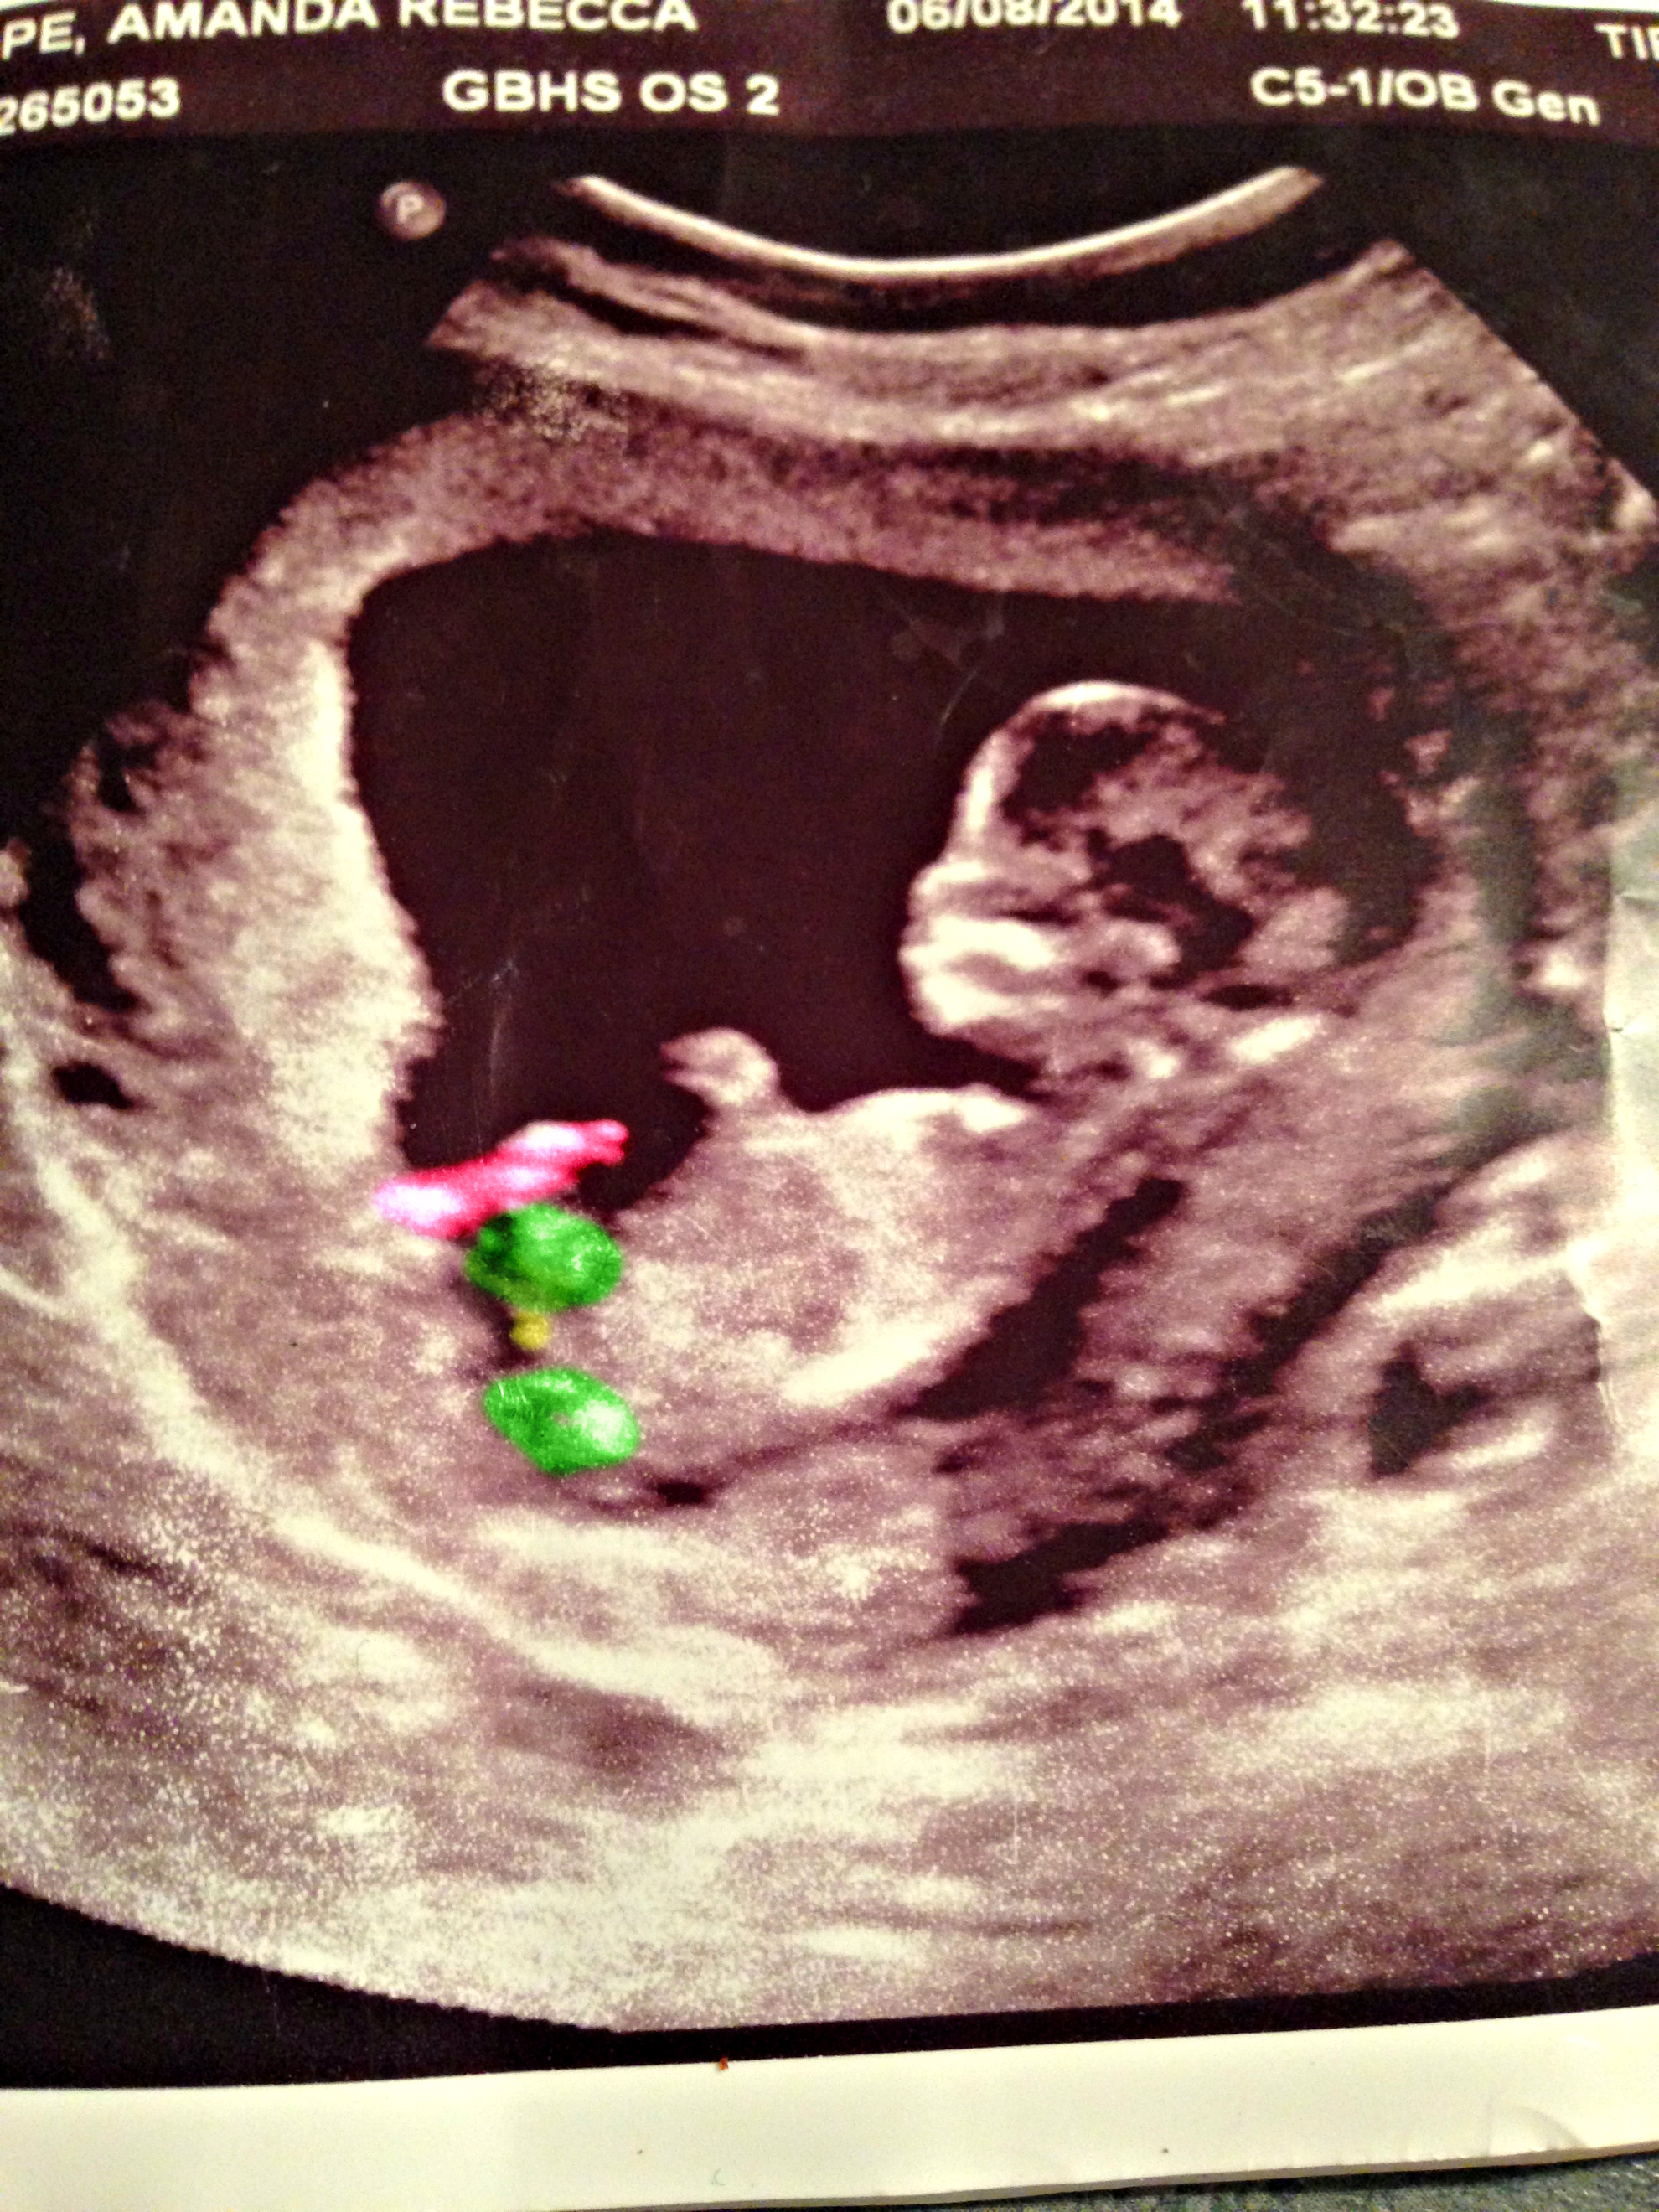

I have posted this photo before but my camera quality was very poor...I just took the same pic with a better camera...This was a 12 week scan...but I believe baby measured over 13 weeks...

I think I see a nub?

Sorry to be annoying, but any clues or is that part of a leg?Attachment 22418Attachment 22418